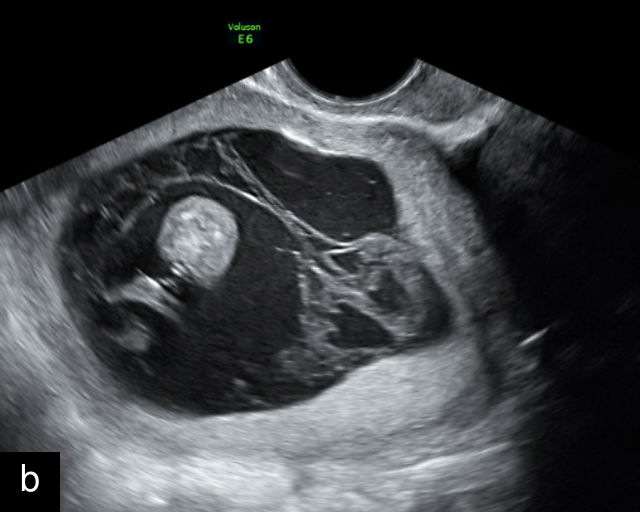

In the early first trimester, trophoblastic tissue appears as an echogenic ring encircling the gestational sac (Figure 1a). By the late first trimester, the placenta becomes recognizable as a distinct structure on ultrasound (Figure 1b). Initially, it presents as a homogeneous echogenic mass (Figure 1b–d) but undergoes progressive differentiation, becoming more heterogeneous as pregnancy advances from the second to third trimester (Figure 1e–g). By the third trimester, cotyledons become discernible, and in the late third trimester, calcifications frequently appear basally and around the cotyledons (Figure 1g).

1

Ultrasound images of development of the placenta (P/p). (a) Trophoblastic tissue appearing as an echogenic ring surrounding the gestational sac at 6 weeks' gestation. (b) Placenta at 12 weeks has become a discrete, uniformly echogenic mass. (c) Placenta at 17 weeks. (d) Placenta at 20 weeks. (e) Placenta at 27 weeks. (f) Placenta at 33 weeks. Increasingly, differentiation and heterogeneous appearance is seen, with demarcation of the cotyledons. Basal calcifications are beginning to appear. (g) Placenta at 40 weeks, showing a distinctly heterogeneous appearance, with clear demarcation of the cotyledons and presence of calcifications.